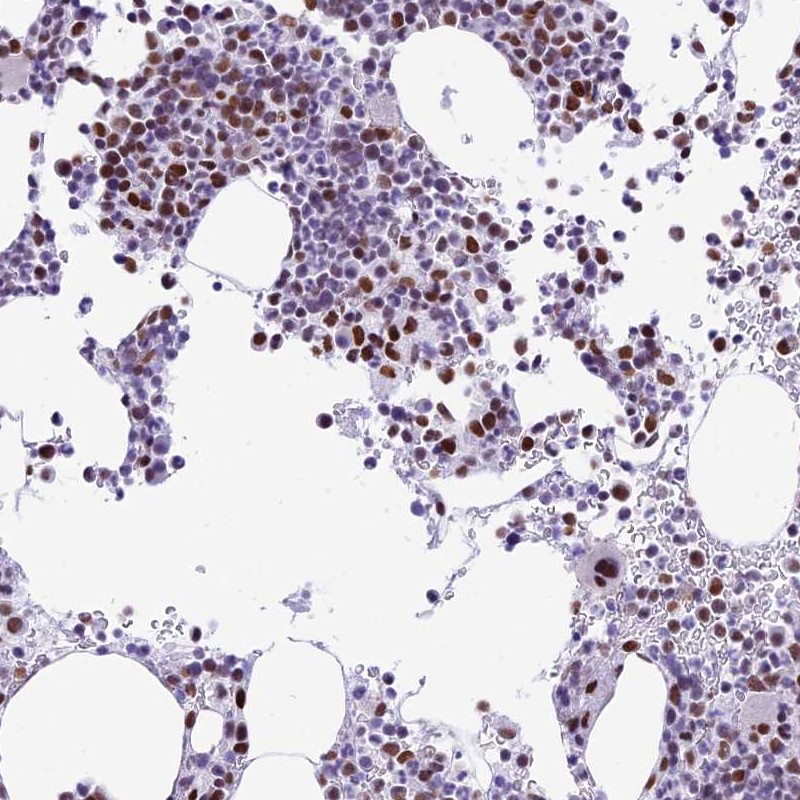

Immunohistochemical staining of human bone marrow shows distinct nuclear positivity in hematopoietic cells.